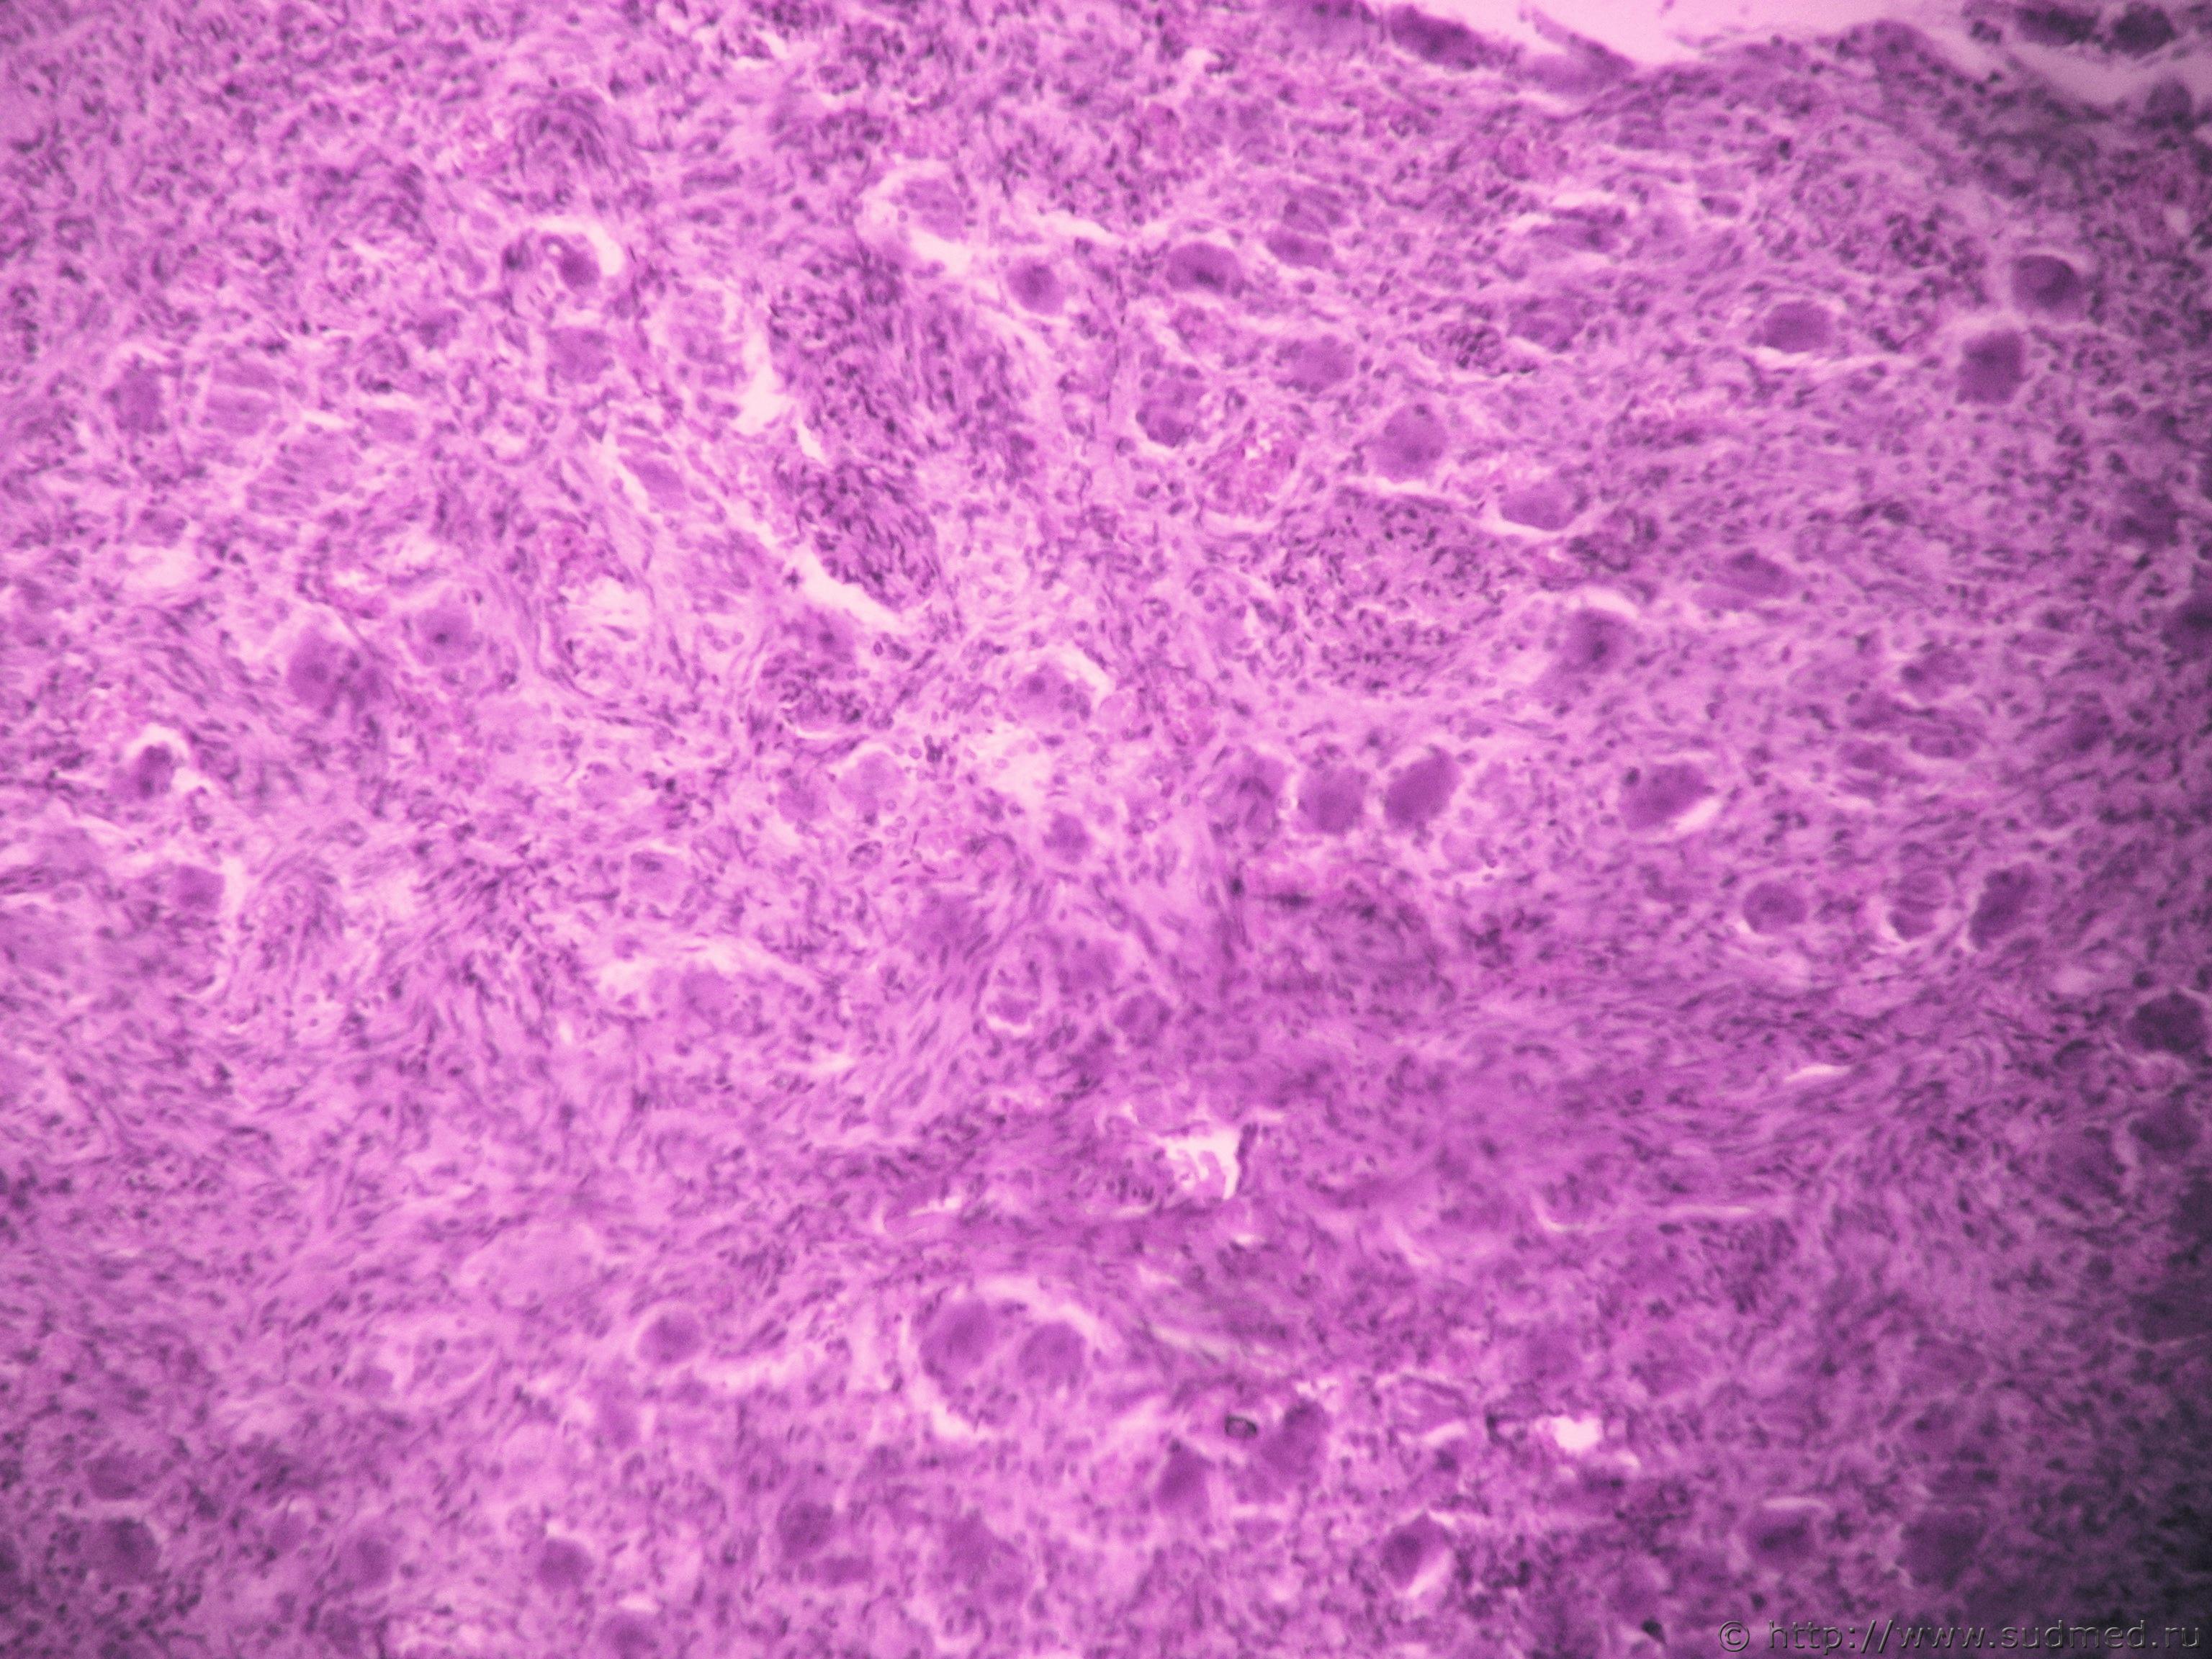

Язва-рак желудка.